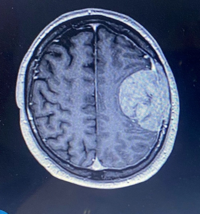

Three weeks later, on May 9, 2025, Stuart underwent seven hours of surgery where surgeons were able to remove the entire tumor.

It had not grown into his brain but was attached to the membrane and skull, part of which had to be removed and reconstructed using bone cement.

Although initial scans suggested only normal post-surgical swelling, a subsequent MRI report revealed Stuart had suffered a stroke.

The stroke occurred in the area responsible for speech and language, and 10 months on, he is still struggling with his speech.